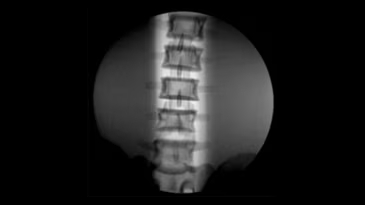

Brivo OEC 785 - это надёжная С-дуга, которая работает вместе с вами, эффективно устраняя сложности визуализации и позволяя хирургу сфокусироваться на пациенте. Отличительной чертой системы Brivo OEC 785 является высокое качество визуализации, на которое можно рассчитывать изо дня в день. Вы можете доверить технологиям GE Healthcare точное и эффективное получение чётких изображений, даже при низкой дозе. Автоматизированные смарт-функции Brivo OEC созданы, чтобы вы получали изображения высокого качества, даже в клинически сложных случаях. Подобно тому, как орлиный глаз может различить движение и малозаметные объекты, эта система делает упор на получение изображения высокой точности при любой степени клинической сложности.

- Четкая визуализация и клиническая надежность

Получение четких изображений с помощью «умной» цепи визуализации. - Удобная работа